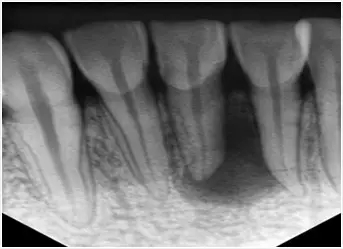

1、術(shù)前拍攝X線片

在根管治療過程中,在根管治療術(shù)前拍X線片,以幫助診斷,了解髓室的位置和根管數(shù)目及形態(tài),測量根管工作長度及日后隨訪和評價療效提供對比的依據(jù)。

1.webp.jpg